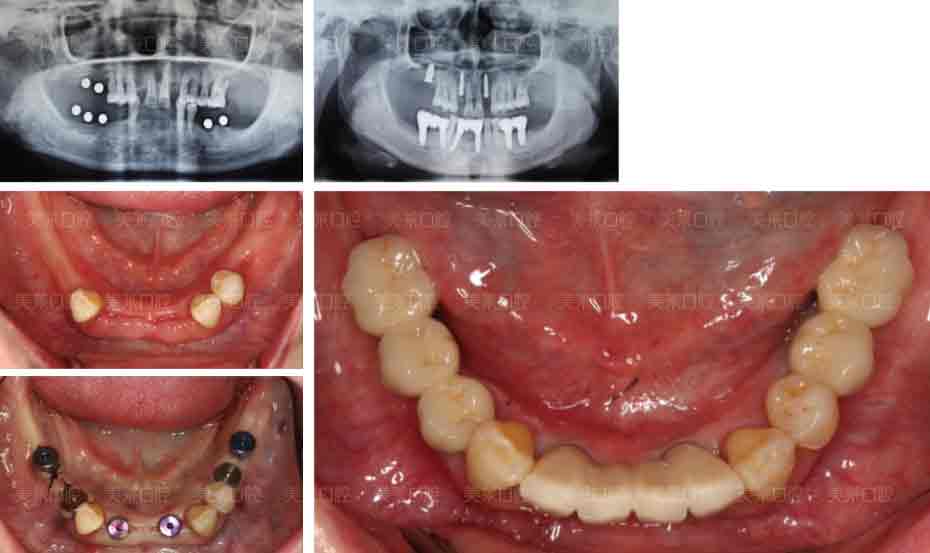

美莱种植牙案例

对牙周病引起的牙齿松动,若轻度松动,通过进行洁治、刮治等治疗措施,大多可恢复正常;若中度松动,在治疗牙周病的同时,还应该把松动牙与相邻的牙固定在一起,用以降低松动牙的负荷,阻止牙齿松动的加重,这时松动的牙齿多数还不能恢复;重度松动的牙齿,也就是牙齿无论在上下左右均明显松动,这时多需要拔除患牙,避免加重邻牙不必要的负担。拔牙后可用种植牙修复缺失牙齿。